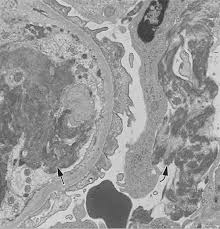

Pdf Postinfectious Glomerulonephritis With Crescents In An Elderly Diabetic Patient After Acute Gastroenteritis Case Report

Pdf Postinfectious Glomerulonephritis With Crescents In An Elderly Diabetic Patient After Acute Gastroenteritis Case Report from www.researchgate.net

The Relevance Between Renal Ultrasonographic Findings And Disease Course In Two Poststreptococcal Glomerulonephritis Psgn Patients

The Relevance Between Renal Ultrasonographic Findings And Disease Course In Two Poststreptococcal Glomerulonephritis Psgn Patients from www.chikd.org